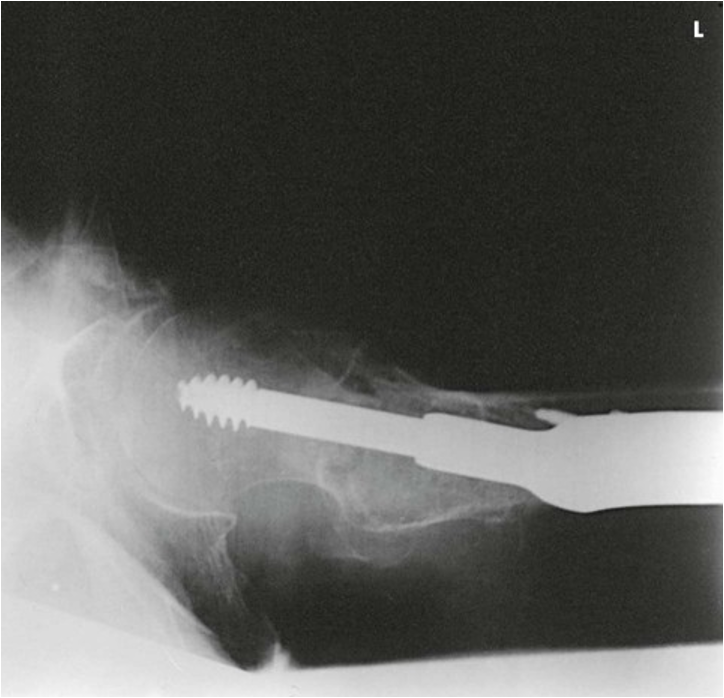

Axiolateral Projection; Hip; Danelius-Miller Method (CR & SS)

Perpendicular to the long axis of the femoral neck. The central ray enters the groin area at a point midway between the anterior and posterior surfaces of the upper thigh and passes through the femoral neck, which is about 2.5 inches (6.4 cm) below the point of intersection of the localization lines

The resulting image shows the acetabulum, head, neck, and trochanters of the femur

Axiolateral Projection; Hip; Danelius-Miller Method (Eval Criteria)

• Evidence of proper collimation

• Hip joint with the acetabulum

• Femoral neck without overlap from the greater trochanter

• Small amount of the lesser trochanter on the posterior surface of the femur

• Small amount of the greater trochanter on the anterior and posterior surfaces of the proximal femur when the femur is properly inverted

• Ischial tuberosity below the femoral head and neck

• Soft tissue shadow of the unaffected thigh not overlapping the hip joint or proximal femur

• Any orthopedic appliance in its entirety

• Soft tissue and bony trabecular detail

Axiolateral Projection; Hip; Danelius-Miller Method